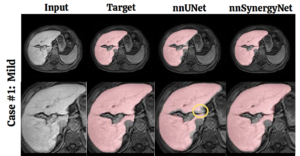

Towards Synergistic Deep Learning Models for Volumetric Cirrhotic Liver Segmentation in MRIs

Authors: Vandan Gorade, Onkar Susladkar, Gorkem Durak, Elif Keles, Ertugrul Aktas, Timurhan Cebeci, Alpay Medetalibeyoglu, Daniela P. Ladner, Debesh Jha, and Ulas Bagci

SPIE Medical Imaging 2025

Publication Year: 2025

SynergyNet: Bridging the Gap Between Discrete and Continuous Representations for Precise Medical Image Segmentation.

Authors: Gorade, Vandan, et al.

WACV 2024

Publication Year: 2024